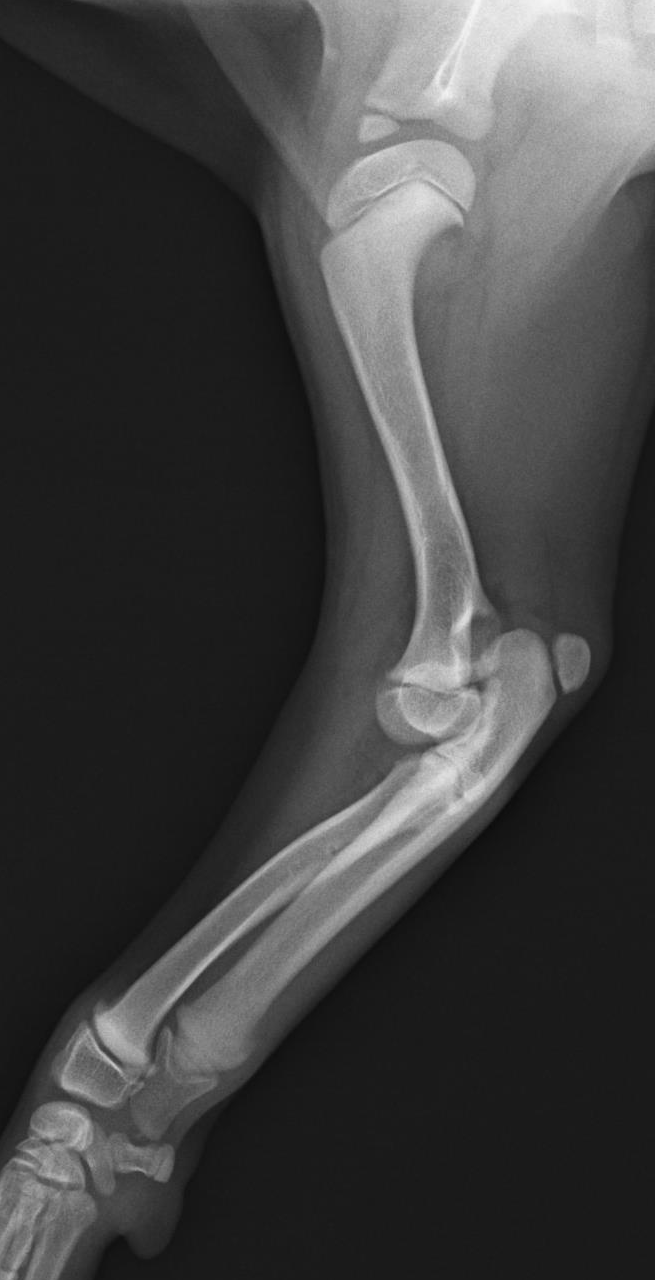

小型犬は高所からの落下などにより前足の骨“橈尺骨”を骨折してしまう事例が多いです。全ての子が手術適応では無く、包帯のみで治療する場合もあります。手術が必要と判断した場合、本院ではチタンプレートやステンレスプレートを体重により使い分け、より正確な治療を行います。海外からプレートを発注し種類も豊富のため、全ての犬種、猫種に対応可能となっております。